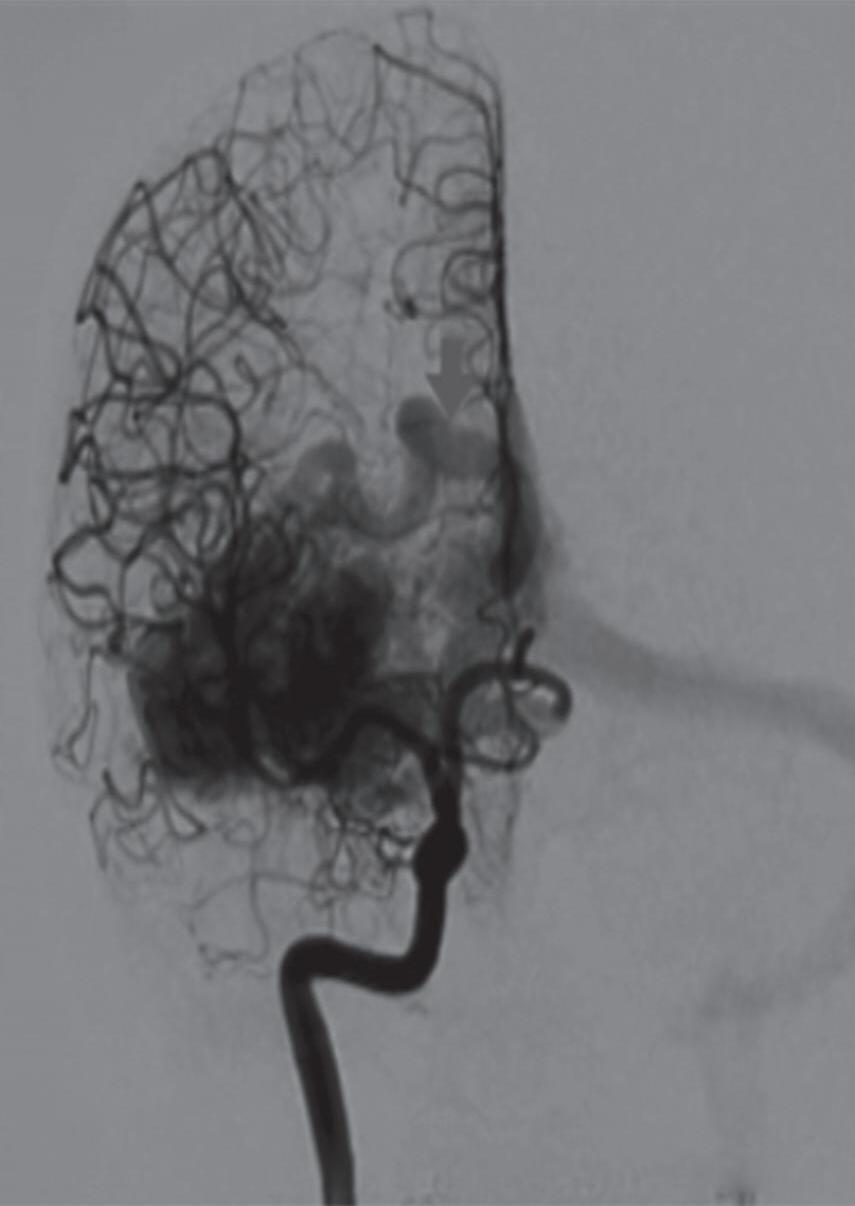

A suspeita diagnóstica das MAVs geralmente é feita por meio de métodos não invasivos de aquisição de imagem, tais como tomografia computadorizada (TC), angiotomografia, ressonância magnética (RNM) e angiorressonância, contudo, as informações anatômicas vasculares necessárias para o planejamento e a execução terapêutica demandam geralmente do estudo dinâmico da angioarquitetura da MAV pela arteriografia cerebral, considerado o exame padrão-ouro para o diagnóstico (Figs. 1-21 e 1-22).35

A arteriografia cerebral digital com subtração é considerada o exame padrão-ouro para avaliação das MAV, possui excelente resolução espacial e temporal, o que é necessário para avaliar o tamanho do nidus, a presença de estenose de artéria nutridora, da veia de drenagem, avaliar a presença de aneurismas arteriais e venosos e o fluxo da malformação. Rotineiramente ela deve ser realizada pelo cateterismo dos seis vasos (carótidas internas, externas e artérias vertebrais) e a descrição do exame necessita conter a localização anatômica da malformação, além dos seguintes achados (Figs. 1-24 e 1-25):

Fig. 1-24. Angiograma anteroposterior mostrando MAV nutrida pelas artérias cerebrais média (ramos precoces) setas azuis, com uma grande veia de drenagem – veia cerebral média profunda, seta vermelha relacionada com a ponta do lobo temporal esquerdo. (a-d) Pré-operatório. (e-h) Pós-operatório, mostrando a ressecção completa da lesão e restabelecimento do fluxo regional.